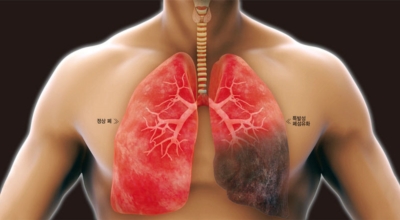

우리나라는 사망률 중 4위가 폐렴일 정도로 폐관련 질환은 위험도가 높다고 합니다. 우리의 몸 면역을 조절해주는 컨트롤 타워가 폐이기 때문에 그만큼 중요하며 호흡기 계통의 질병이 대부분 폐와 관련이 있기 때문에 폐 건강을 항상 챙겨두는 것이 좋습니다. 호흡기 건강, 폐 건강에 있어서는 비타민과 미네랄 그리고 항산화제가 풍부한 음식 몇 가지만 추가해도 체내의 염증을 줄이고 폐 기능을 개선하며 호흡기 건강을 증진시키는데 도움이 될 수 있습니다. 그럼 폐에 좋은 음식 10 가지를 알아보겠습니다.

폐이미지